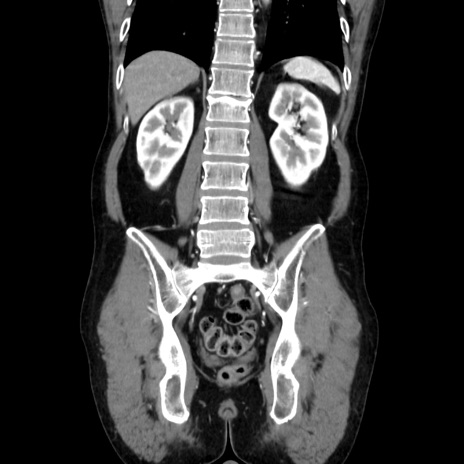

症例37(冠状断像)

【症例】40歳代 男性

【主訴】腹痛

【現病歴】4時間ほど前に電車に乗車中に臍部上より腹痛出現。徐々に増悪し起立困難となり、救急外来受診。生ものは数日食べていない。今朝お雑煮を食べた。

【身体所見】BT 36.8℃、BP 117/84mmHg、HR 91/min、SpO2 97%、苦悶様、腹部:臍上部広範囲圧痛あり、反跳痛±

【データ】WBC 8100、CRP 0.03